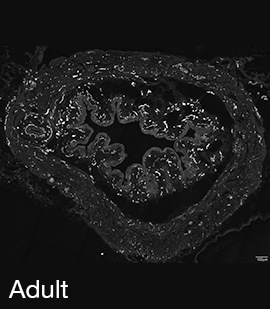

Figure 3A: Structure of peptidergic sensory axons in the bladder (adult mouse).

Examples of sensory axons immunolabelled for calcitonin gene-related peptide (CGRP; Calca) in cryosections of mouse bladder at E16 (See GUDMAP RID N-FM22), P2 (See GUDMAP RID N-FN1T) and adult (See GUDMAP RID N-FNF2).